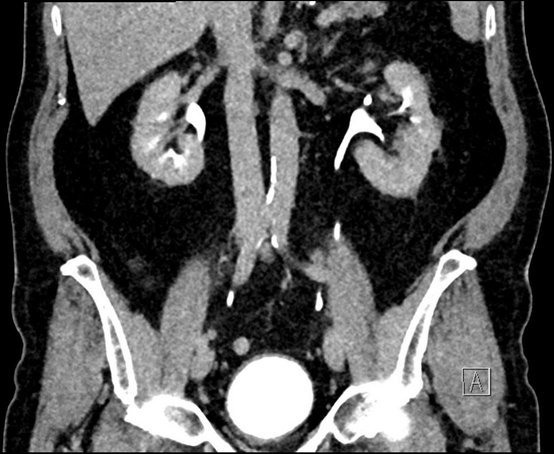

CT-Aufnahme eines Nierentumors zur urologischen Diagnose und Therapie.

Eine CT-Aufnahme eines Nierentumors.

Früherkennung und Behandlung von Nieren- und Harnleitertumor

Tumore der Niere und des Harnleiters sind selten und können dank moderner Medizin häufig frühzeitig erkannt und organerhaltend behandelt werden. Neben hochmodernster Diagnostik steht Ihnen in unserer Klinik für Urologie das gesamte Spektrum der operativen und medikamentösen Therapie zur Verfügung.

Hierbei orientieren wir uns stets an den neuesten Leitlinien und Forschungserkenntnissen. Die Wahl der Therapie ist dabei von der Tumorart, der Tumorgröße und Lage abhängig und orientiert sich stets an der Patientensituation.